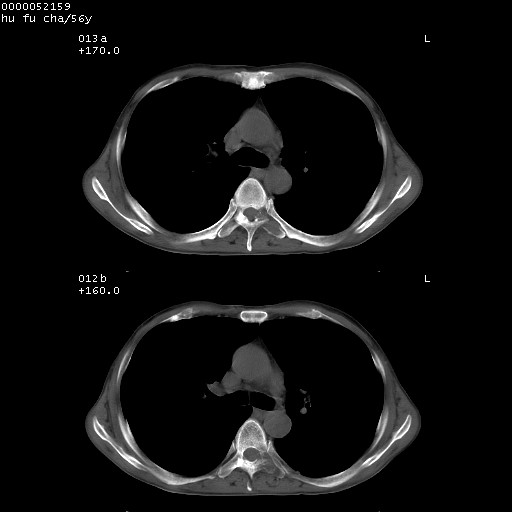

以下是引用zsl6918在2008-8-25 22:47:00的发言:[br]胸骨,胸椎及肋骨均可见多发转移表现,肝内低密度结节不除外转移。原发灶可能在右肺。双侧可见支扩表现。

以下是引用宇宙ct在2008-8-25 23:26:00的发言:[br][br] 胸骨,胸椎及肋骨均可见多发转移表现,肝内低密度结节不除外转移。原发灶可能在右肺。双侧可见支扩表现。 [br] [br]

以下是引用卜一在2008-8-26 8:02:00的发言:[br][br] 支持:肺癌并肺内,胸骨,胁骨,胸椎及肝内转移!另:左肺支气管扩张征伴感染! [br]

以下是引用zjzjr在2008-8-26 11:03:00的发言:[br]支持:肺癌并肺内,胸骨,胁骨,胸椎及肝内转移!另:左肺支气管扩张征伴感染!